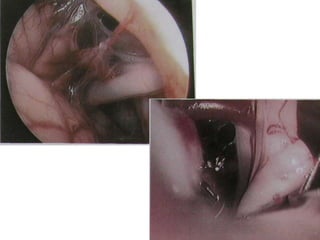

A nontoothed forceps is used to hold the soft tissues (ST) surrounding

the nerve at the level of the stylomastoid foramen (SMF), and

sharp scissors are used to dissect the soft tissues from the bone at that

level. C Cochlea, FN(m) Mastoid segment of the facial nerve, LSC Lateral

semicircular canal, NC New canal, SS Sigmoid sinus

Rerouting of the facial nerve. FN(m) Mastoid

segment of the

facial nerve, FN(p) Intraparotid facial nerve, SM

Facial nerve at the stylomastoid

level, ST Soft tissues

The facial nerve has been rerouted into the new

canal (*).

FC Fallopian canal, FN(p) Rerouted part of the

intratemporal facial nerve,

FN(t) Rerouted part of the tympanic segment of

the facial nerve, ST Soft

tissues